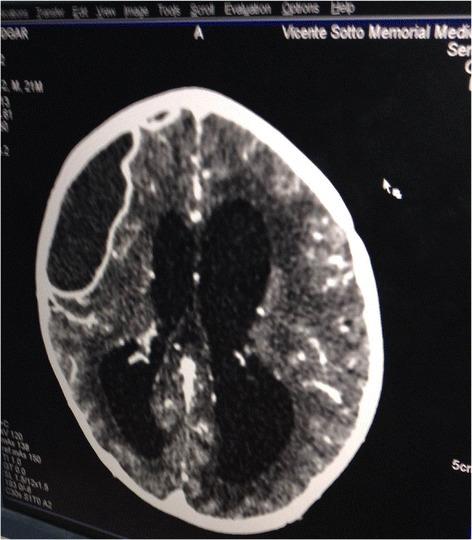

We present a case of a child with a suspected brain abscess treated by a military field hospital in post-typhoon Philippines. We review our intervention and decision process both at the field hospital and following his transfer to a referral center. These interventions were critical for his successful outcome.

我们介绍了一名疑似脑脓肿儿童的病例,该病例由菲律宾台风过后的一家军队野战医院进行治疗。我们回顾了在野战医院以及他转至转诊中心后的干预措施和决策过程。这些干预措施对其成功康复至关重要。